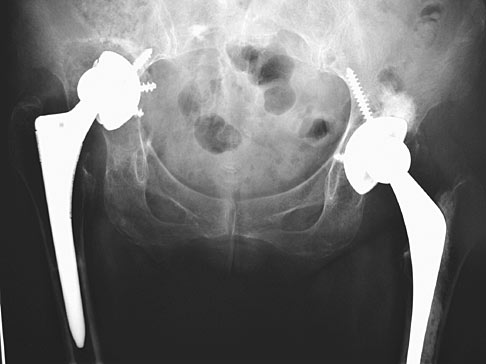

A modular solution for severe acetabular defects and pelvic discontinuity. This application utilizes a proprietary porous lattice structure to promote rapid bone in-growth and secondary stability. The engineered scaffolds provide the structural rigidity necessary for high-stress weight-bearing while maintaining a modulus of elasticity near that of native cancellous bone.